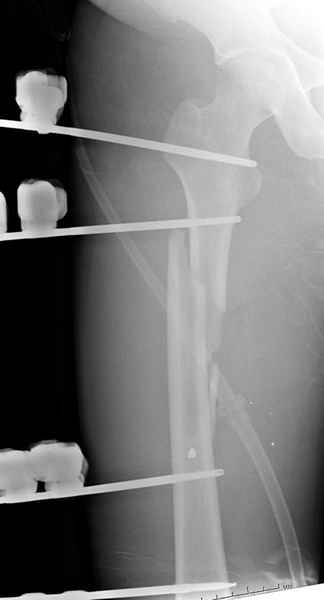

Второй случай тоже репозиция из малого доступа, больному 19 лет, множественные огнестрельные повреждениия конечностей, живота и черепа, правая конечность холодная, без пульсации. Ортопедический диагноз: огнестрельный перелом правого бедра. При срочной ангиографии повреждения сосудов не подтвердилось, конечность из-за ургентности состояния больного зафиксирована временным наружным фиксатором и больной оставлен на операционном столе для срочной лапаротомии хирургической службой.

Больной долго оставался нестабильным, только на 14 день удалось заменить на антеградный интромедуллярный штифт TFN (trochanteric femoral nail) SmithNephew. После неудачной попытки закрытой репозиции, несмотря на использование "joystick", проксимальный стержень от

наружного фиксатора, (перелом начал срастаться) репозицию провели из малого доступа, затем остальные этапы операции.

Случай был представлен из-за того, что больного оперировали после наружной фиксации и был риск инфекцирования через места проведения стержней (на снимках), прошло больше 3 месяцев, выписан из амбулаторной службы из-за отсутсвия надобности дальнейшего наблюдения.